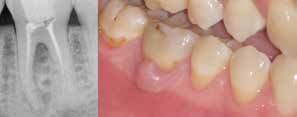

Fase diagnostica, che prevede una prima anamnesi clinica, una radiografia pre-operatoria per interpretare l’anatomia endodontica, al fine di definire un corretto piano di trattamento.

La diagnosi in endodonzia non può prescindere dall’esecuzione di esami radiologici accurati, in grado di mostrare l’esatta anatomia delle strutture dentali, in particolare dell’anatomia radicolare e dei tessuti di supporto.